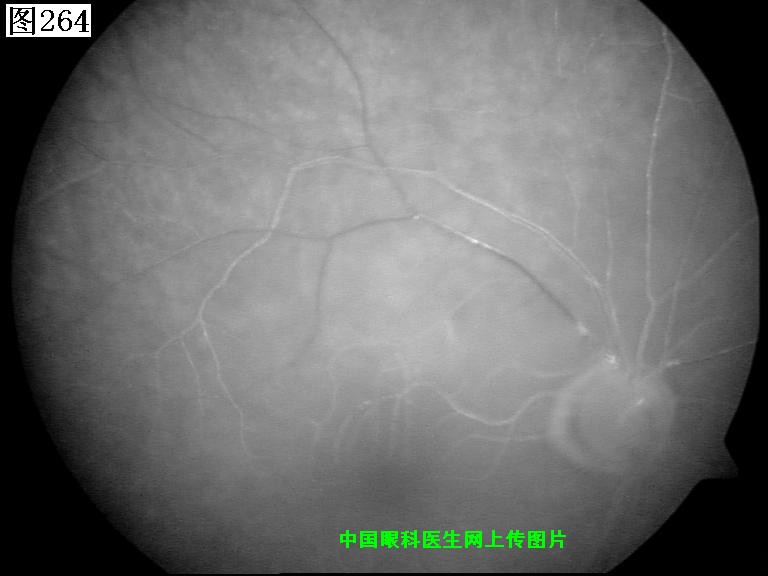

261 262 263 264